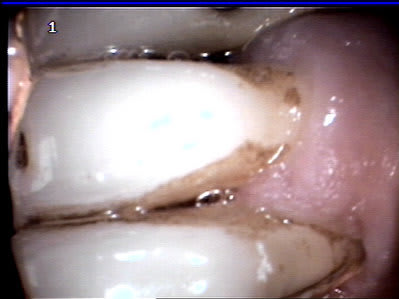

et c'est classé. tres bine pour les motivations et communiquer avec le patient , mais encore faut il que tout soit à poste. le boitier n'est pas bine gros; il me reste juste a fixer le petit support pour la camera; en passant elle eest plus petite que pas mal de modele que j'ai vu.